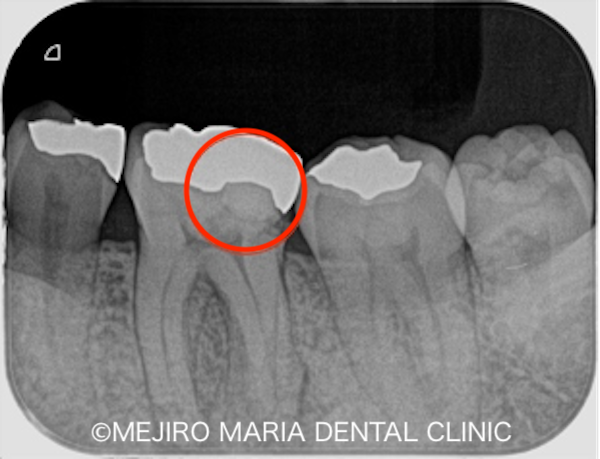

レントゲン写真で確認すると、金属の詰め物の下に虫歯を示す黒い影(写真中央の赤丸)と、歯の根の先端(根尖)にも黒い影が確認できました。歯髄診査を行って初診時の状態を調べたところ、歯髄に生活反応(神経が生きているか)は確認できず、歯髄は既に壊死を起こしている状態でした。